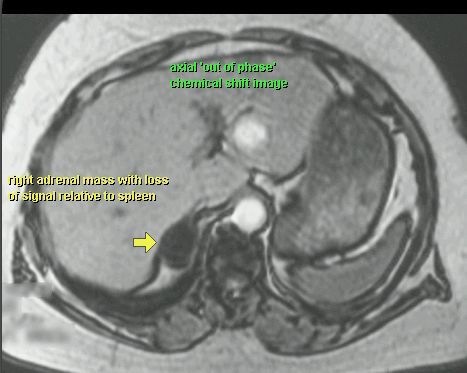

GRUCZOLAK NADNERCZA

MR